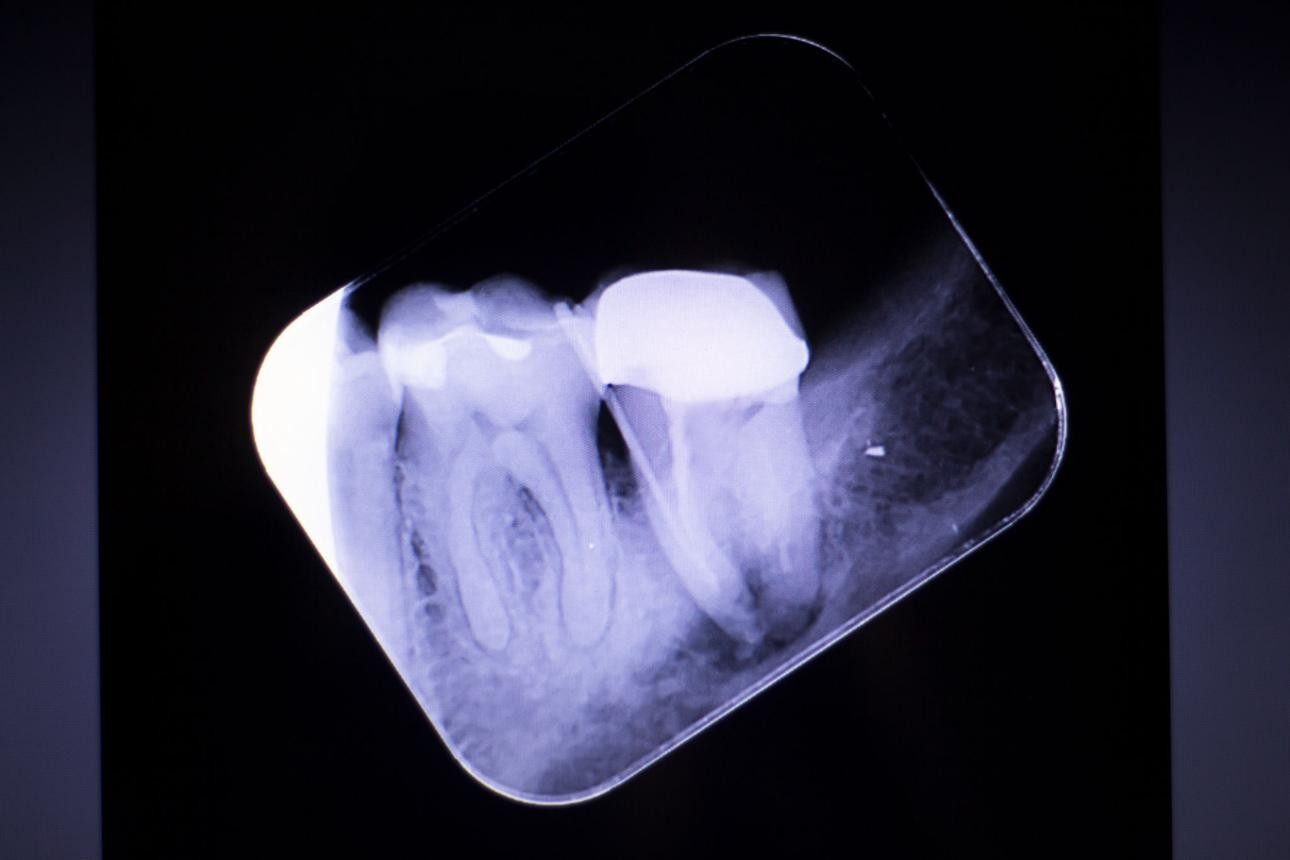

4. Dental X-Rays (Most Important Step)

X-rays play a crucial role in diagnosing the need for RCT

treatment. They help dentists see:

- Infection at the root tip

- Bone loss around the tooth

- Deep cavities reaching the pulp

If the infection is visible on an X-ray, root canal treatment in

Bangalore is usually necessary.